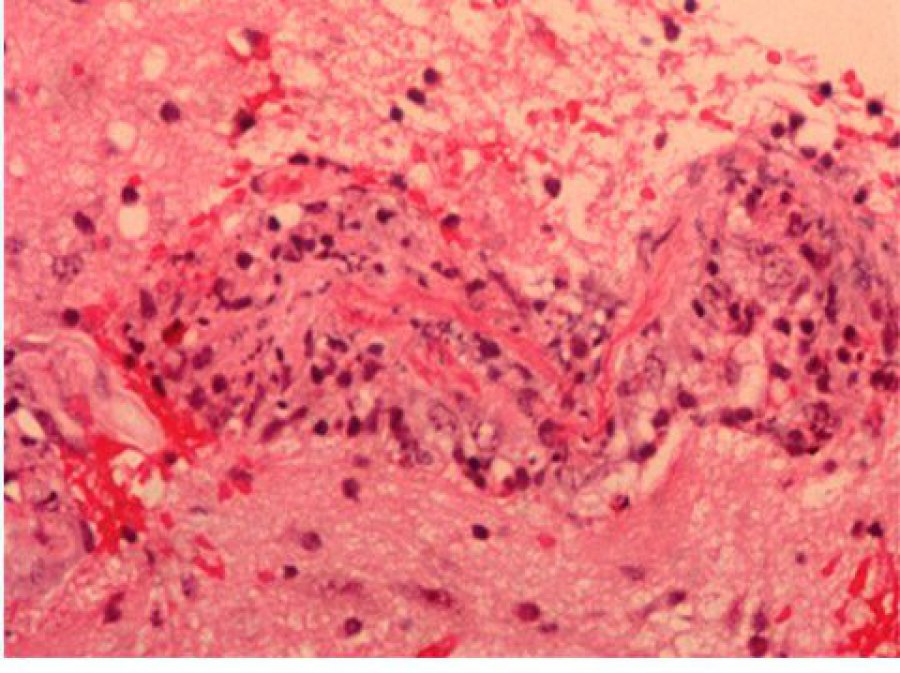

Learn MoreTumours and Cysts

High grade, low grade, benign and non-neoplastic mass lesions of the brain and spine in adults and children